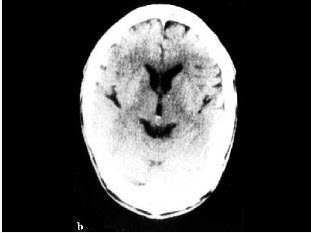

男,32岁,确诊左颞叶胶质母细胞瘤Ⅳ级,手术切除病灶,术后放疗2个月,化疗3个疗程;现距放疗结束17个月。查体:右上肢轻度乏力,骶尾部及双足麻木,排便困难;检查:MRI示左颞叶肿瘤局部复发可能。行PET/CT显像全身检查如图。最可能的诊断()。

A.左侧颞叶术后瘢痕组织改变

B.左侧颞叶肿瘤复发

C.恶性肿瘤沿椎管种植性转移

D.马尾种植性转移灶

E.以上都不是